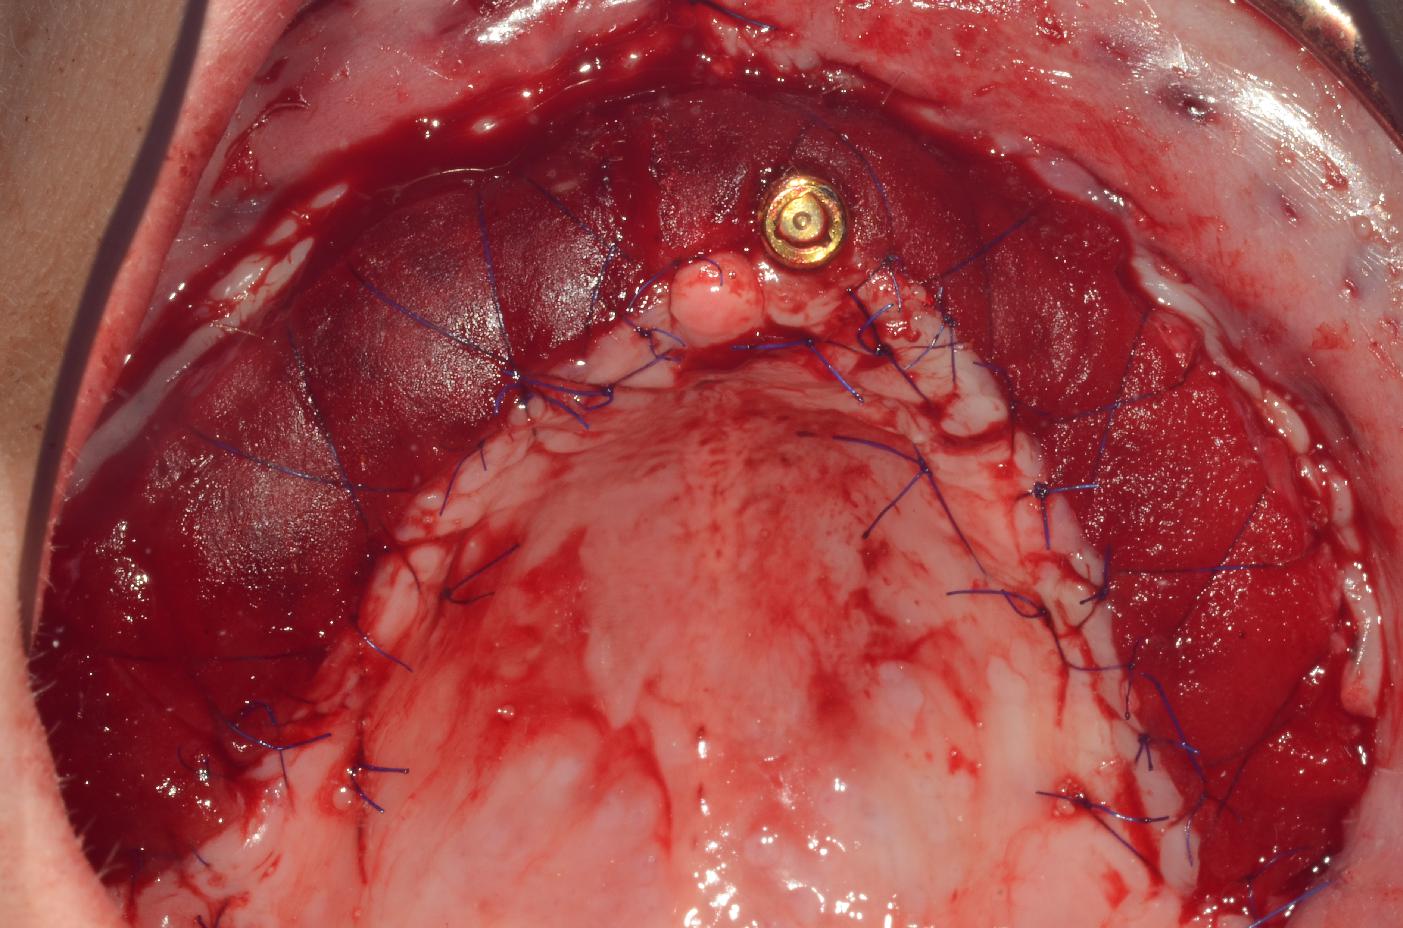

3/8 - mucoderm® fixation with single and cross-suturesmucoderm® for full arch reconstruction of insufficient vestibular depth and lack of keratinized tissues - Dr. B. Mólnar & Prof. P. Windisch

4/8 - mucoderm® fixation with single- and cross-suturesmucoderm® for full arch reconstruction of insufficient vestibular depth and lack of keratinized tissues - Dr. B. Mólnar & Prof. P. Windisch